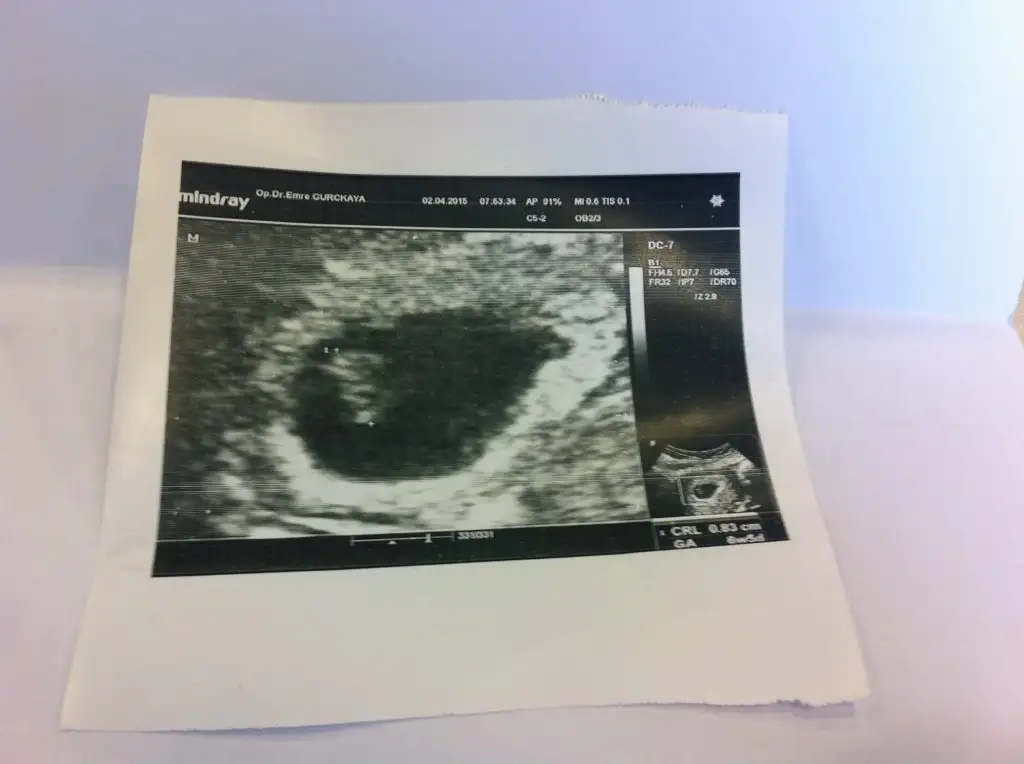

Kızlar benim son adet tarihi 21 Şubat şu an 6+6 ilk ultrason görüntüleri tahminlerinizi bekliyorumm :KK15: